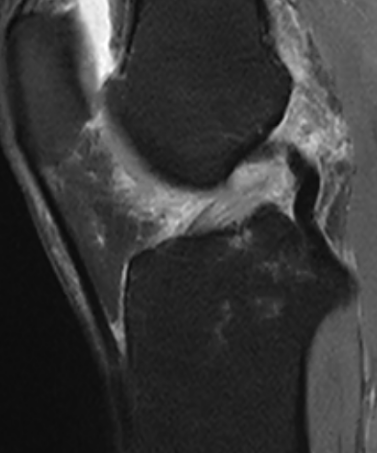

接诊的刘志强副主任医师查体发现其左膝关节肿胀明显,触压痛明显,结合膝关节核磁共振检查结果,诊断为:1. 左膝前交叉韧带断裂;2. 左膝内侧副韧带损伤。

术前核磁共振提示膝关节前交叉韧带断裂